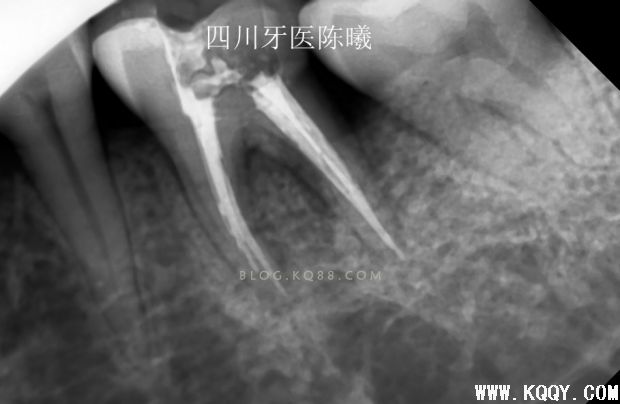

上次根管预备的测长片,当时为了做好就已经在预备后照了试尖片!可惜还是没有料到充填会有这么麻烦!

试尖后发现远颊主尖选择错误,由于是在预备的时候,所以也没有继续试,只是在病人收费票据上写清了个牙根情况!告知患者复诊时带来!(看到这您会问为什么不用病例,因为选择上班的地方都没有写小病例给病人的习惯,所以我也没有写,但是经过这个病例,在考虑以后根管治疗的病人都应该给病人一个病历本了!因为这个问题,成了造成后面问题的原因之一)